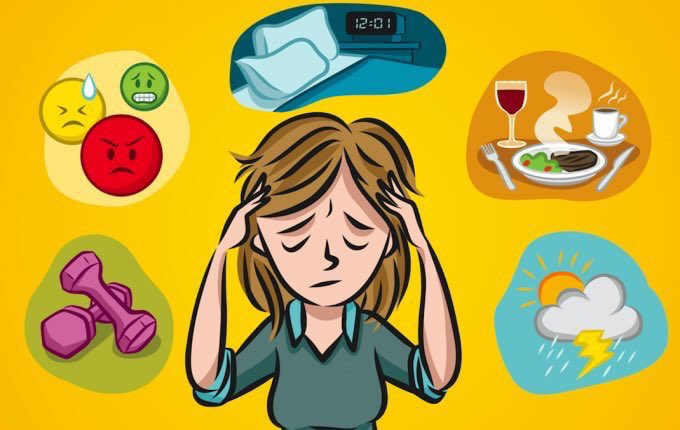

نفسياً

العلاقة بين #القولون_العصبي والمشاكل والأمراض النفسية علاقة مهمة ووطيدة

العلاقة بين #القولون_العصبي والمشاكل والأمراض النفسية علاقة مهمة ووطيدة

* ممارسة النشاط البدني بشكل منتظم للتقليل من التوتر وتحفيز الانقباضات الطبيعية لعضلات الأمعاء.

* الحد من التوتر، وذلك عن طريق التنفس العميق والاسترخاء وغيرهما.

* الحد من التوتر، وذلك عن طريق التنفس العميق والاسترخاء وغيرهما.